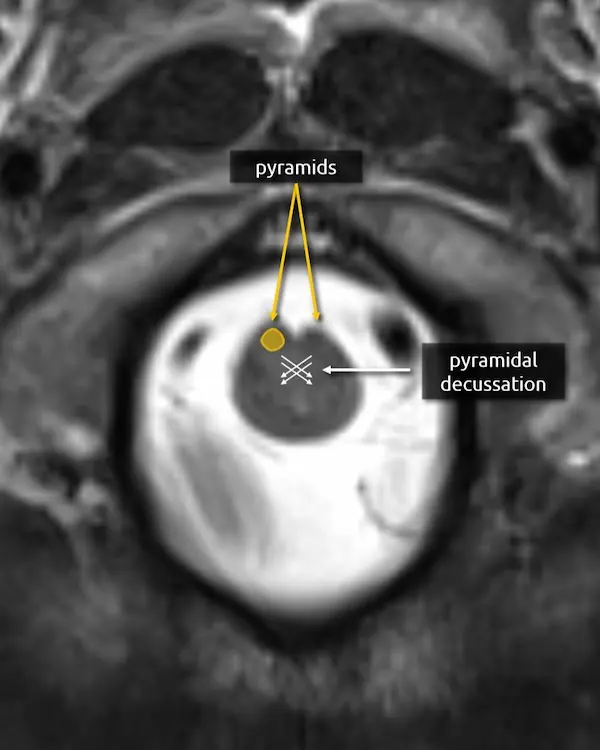

1. Pyramids:

The medullary pyramids contain the corticospinal tract and corticobulbar tract, which are sometimes collectively called the pyramidal tracts. They are named due to the shape they form on the ventral surface of the medulla, which usually becomes more pyramid-like inferiorly.

1. Pyramids

2. Pyramidal decussation:

The medulla transitions to the cervical spinal cord at about the level of the craniocervical junction. Right before this transition, about 90% of the corticospinal tract fibers traveling through the pyramids cross the pyramidal decussation before continuing through the spinal cord as the lateral corticospinal tract. The other 10% form the anterior corticospinal tract. On cross-sectional imaging, the approximate location of the decussation is inferred using the skull base and foramen magnum as landmarks.